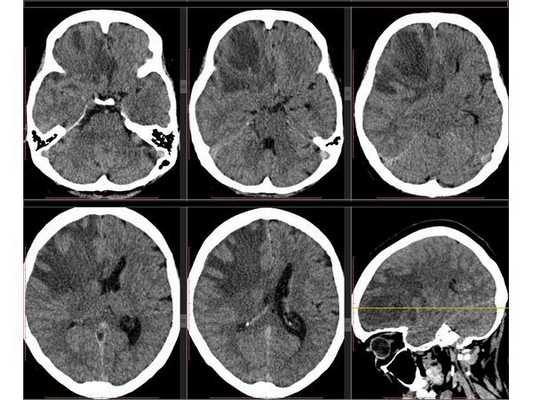

Рентгенография лёгких: без патологии. УЗИ органов брюшной полости: выявлены хронический холецистит, хронический панкреатит, диффузные изменения печени и поджелудочной железы. ЭКГ: в норме. На КТ головного мозга визуализировалось объёмное образование в правой лобной доли. Это вызвало подозрение на абсцесс, но отсутствие уровня жидкости, лихорадки и менингеального синдрома у пациентки в большей степени склонило клиническую мысль в сторону онкологического поражения. В связи с этим пациентку госпитализировали в отделении неврологии. Однако при осмотре онкологом и гинекологом данных, которые бы подтверждали наличие онкологии головного мозга, обнаружено не было. В качестве дообследования проведена КТ головного мозга с контрастным усилением. Она выявила объёмное образование в правой лобной доли с чётко очерченной капсулой. Рядом с образованием располагался отёк, срединные структуры были смещены влево примерно на 5 мм.

3D-реконструкция объёмного образования правой лобной доли головного мозга, выполненная на основании сканов КТ с контрастным усилением

Точность диагностирования с помощью КТ головного мозга зависит от стадии формирования абсцесса. На ранних стадиях заболевания диагностика затруднена. На этапе раннего энцефалита (1-3 сутки) КТ определяет зону сниженной плотности неправильной формы. Введенное контрастное вещество накапливается неравномерно, преимущественно периферических отделах очага, реже в центре.

На более поздних этапах энцефалита контуры очага приобретают ровные округлые очертания. Контрастное вещество распределяется равномерно, по всей периферии очага; плотность центральной зоны очага при этом не меняется. Однако на повторной КТ (через 30-40 минут) определяется диффузия контраста в центр капсулы, а также наличие его и в периферической зоне, что не характерно для злокачественных новообразований.

Инкапсулированный абсцесс мозга на КТ имеет вид округлого объемного образования с четкими ровными контурами повышенной плотности (фиброзная капсула). В центре капсулы зона пониженной плотности (гной), по периферии видна зона отека. Введенное контрастное вещество накапливается в виде кольца (по контуру фиброзной капсулы) с небольшой прилежащей зоной глиоза.

На повторной КТ (через 30-40 минут) контрастное вещество не определяется. При исследовании результатов компьютерной томографии следует учесть, что противовоспалительные препараты (глюкокортикостероиды, салицилаты) в значительной степени влияют на скопление контраста в энцефалитическом очаге.